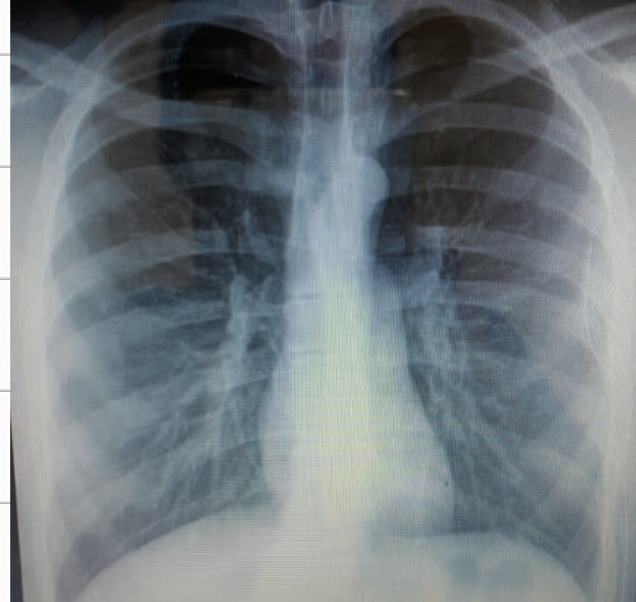

32 year female presented with fever & weight loss

Describe radiological findings

What’s the abnormal here? You should read the whole chest film PA VIEW:

- The trachea looks central.

- Heart looks normal in shape and size.

- What’s abnormal? You have all this reticular shadows and nodules all over the lungs,

Bronchitis does not give a picture like this while miliary TB is a possibility.

differential diagnosis of miliary shadow of the lung?

1- Miliary TB

2- Sarcoid

3- Diffuse metastatic lesions.

4- Lymphomas

5- Silicosis

32 year male presented with fever & weight loss

-

Describe radiological findings?

a. Miliary shadow

b. Bilateral reticular shadow—with sligh tracheal deviation to the right -

List two causes?

a. Miliary TB

b. Fungal infection